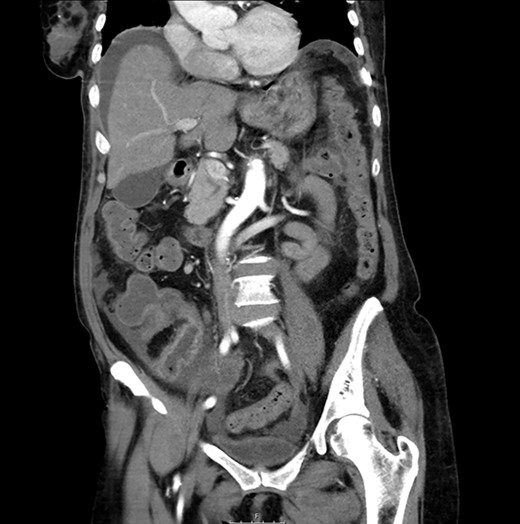

The laboratory results rebelled leukocytosis (15.23x10e3), anemia (9.6 g/dl), neutrophilia (80.4%), band neutrophils in peripheral blood (15%), an elevated C reactive protein (20.62 mg/dl), and procalcitonin (3.92 ng/dl) values (Figs 1 and 2).

CT scan: sudden change of caliber at the terminal ileum together with signs of intestinal suffering.